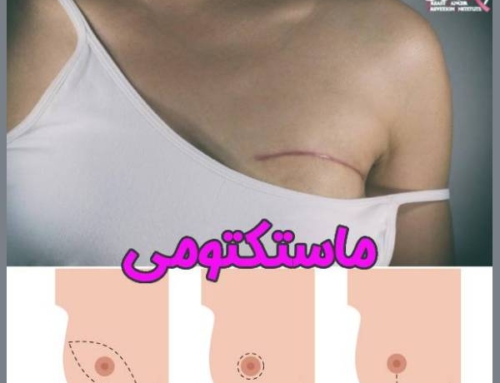

- برداشتن کامل پستان : برداشتن کامل پستان یا ماستکتومی ، در مواردی که نتوان پستان را نگه داشت و درمان های دیگر قابل انجام نباشد ؛ صورت می گیرد. در این نوع درمان سرطان سینه ، غدد لنفاوی زیر بغل نیز مورد بررسی قرار می گیرند. ( اولین جایی که سلول سرطانی سینه گسترش می یابد ، غدد لنفاوی زیر بغل می باشد. )